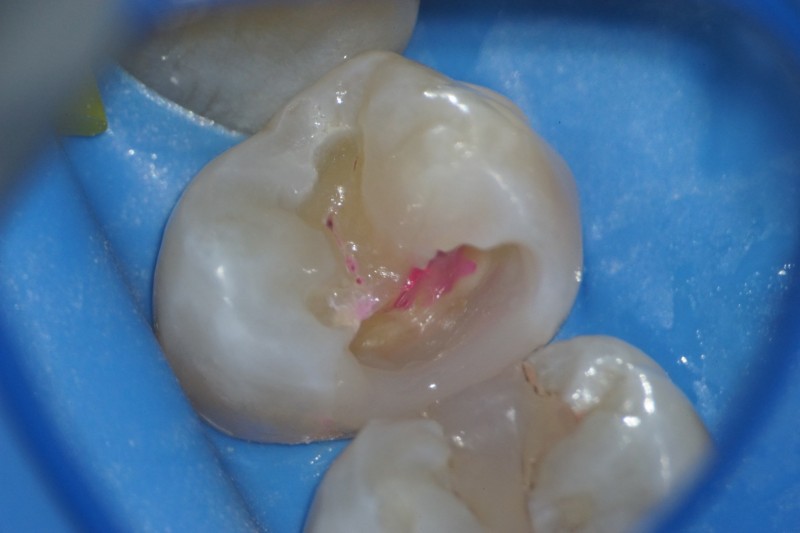

詰め物を外してみると、中が深い虫歯になっています。

ボロボロになっています。

う蝕検知液で残っている虫歯を確認します。

虫歯を除去すると、神経が露出しました。

神経を保護するセメントを詰めます。